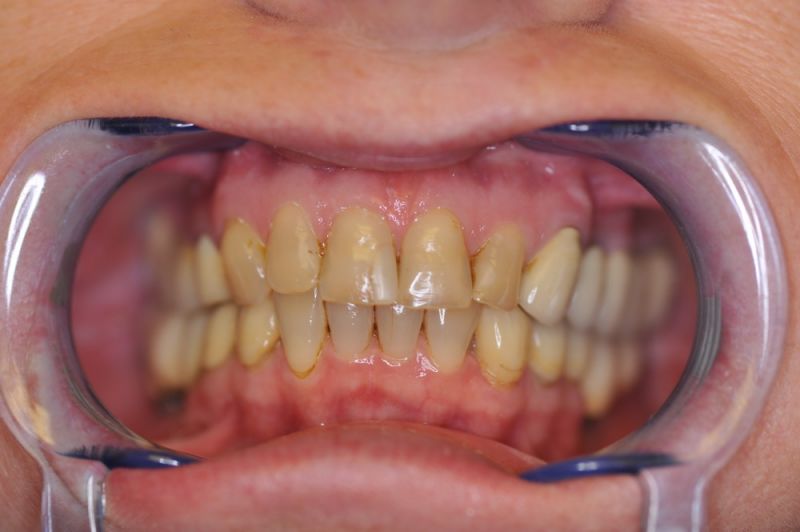

Es war eine Kombination aus Schmerzen bis an die Suizidgrenze, beschränkten wirtschaftlichen Möglichkeiten, sehr stark eingeschränkten Möglichkeiten der für Implantate zur Verfügung stehenden Knochenverhältnisse in einem stark atrophierten Unterkieferseitenzahnbereich und zudem dann auch noch durch auftretenden Problemen bei der Implantatinsertion und nachfolgenden Versorgung der Implantate.

Alle 3 Monate Recall! Das ist jetzt Pflicht für diese Patientin und zwar so lange, so lange sie mit dieser Arbeit durch die Gegend laufen möchte! Und eiserne Disziplin bei der Mundhygiene!